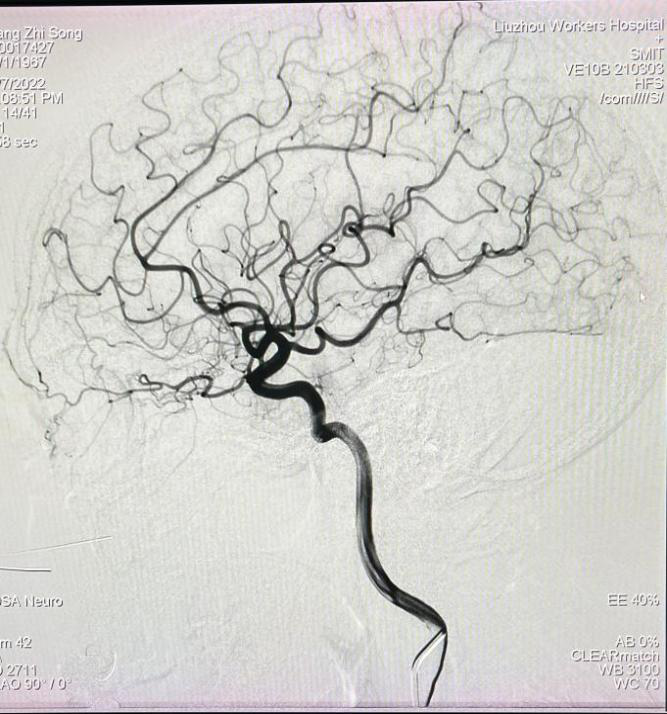

颅脑血管造影

数字减影血管造影的原理是将注入造影剂前后拍摄的两帧X线图像经数字化输入图像计算机,通过减影、增强和再成像过程来获得清晰的纯血管影像,同时实时地显现血管影。

介入治疗室拥有5台先进的数字减影血管造影系统、1台滑轨CT等介入治疗设备、2间复合手术室。主要承担外周、心内、神经、综合(含非血管与血管)介入治疗,包括:血管外科、神经外科、神经内科、心血管内科、肾脏内科、肝胆外科、肿瘤科、消化内科、疼痛科等亚专业,可开展卫生计生委介入诊疗规范化的Ⅰ~Ⅳ级所有介入手术,年手术量逾12000台次。